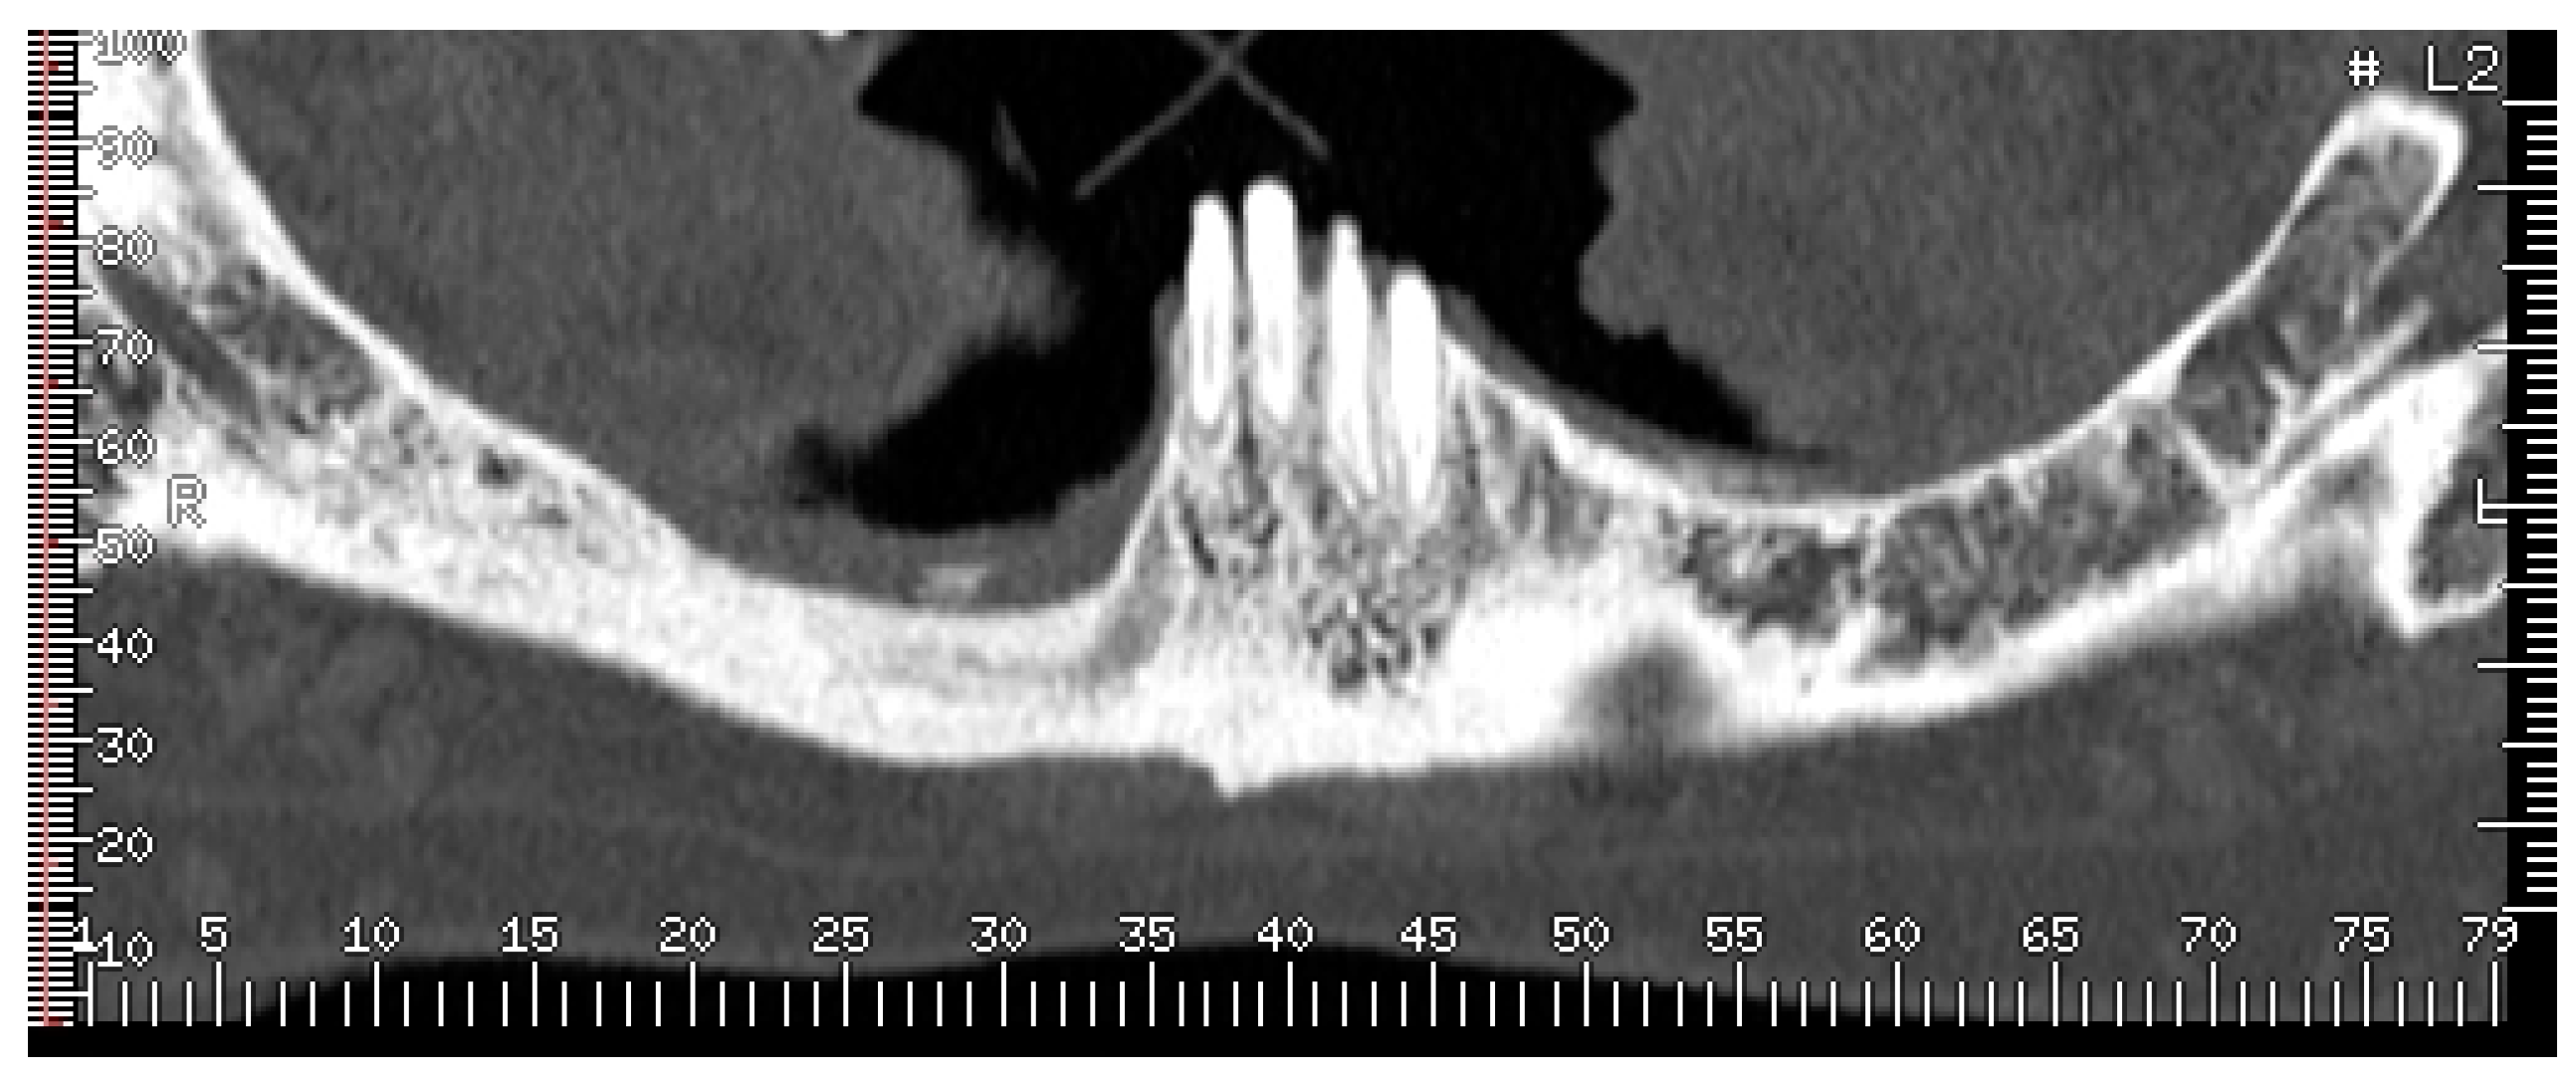

- Bedogni, A.; Fedele, S.; Bedogni, G.; Scoletta, M.; Favia, G.; Colella, G.; Agrillo, A.; Bettini, G.; Di Fede, O.; Oteri, G.; et al. Staging of osteonecrosis of the jaw requires computed tomography for accurate definition of the extent of bony disease. Br. J. Oral Maxillofac. Surg. 2014, 52, 603–608. [Google Scholar] [CrossRef] [PubMed]

- Wilde, F.; Heufelder, M.; Lorenz, K.; Liese, S.; Liese, J.; Helmrich, J.; Schramm, A.; Hemprich, A.; Hirsch, E.; Winter, K. Prevalence of cone beam computed tomography imaging findings according to the clinical stage of bisphosphonate-related osteonecrosis of the jaw. Oral Surg. Oral Med. Oral Pathol. Oral Radiol. 2012, 114, 804–811. [Google Scholar] [CrossRef] [PubMed]